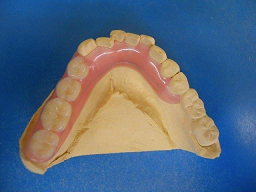

内容 :グラディアダイレクトというのは、〈健保適用外〉の光重合型審美修復用コンポジットレジンで、透明性の異なるペーストの積層築盛で、自然な美しさを再現できる材料です。

グラディアダイレクトの、いいことは、歯を削らなくてもいいという所です。型を採る必要もありません。とても安全で、歯にやさしい方法です。